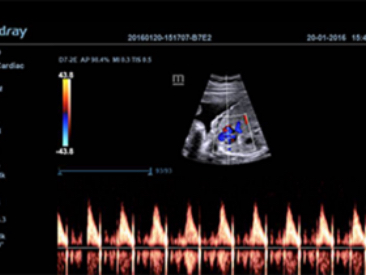

Klinik G?rĂŒntĂŒler